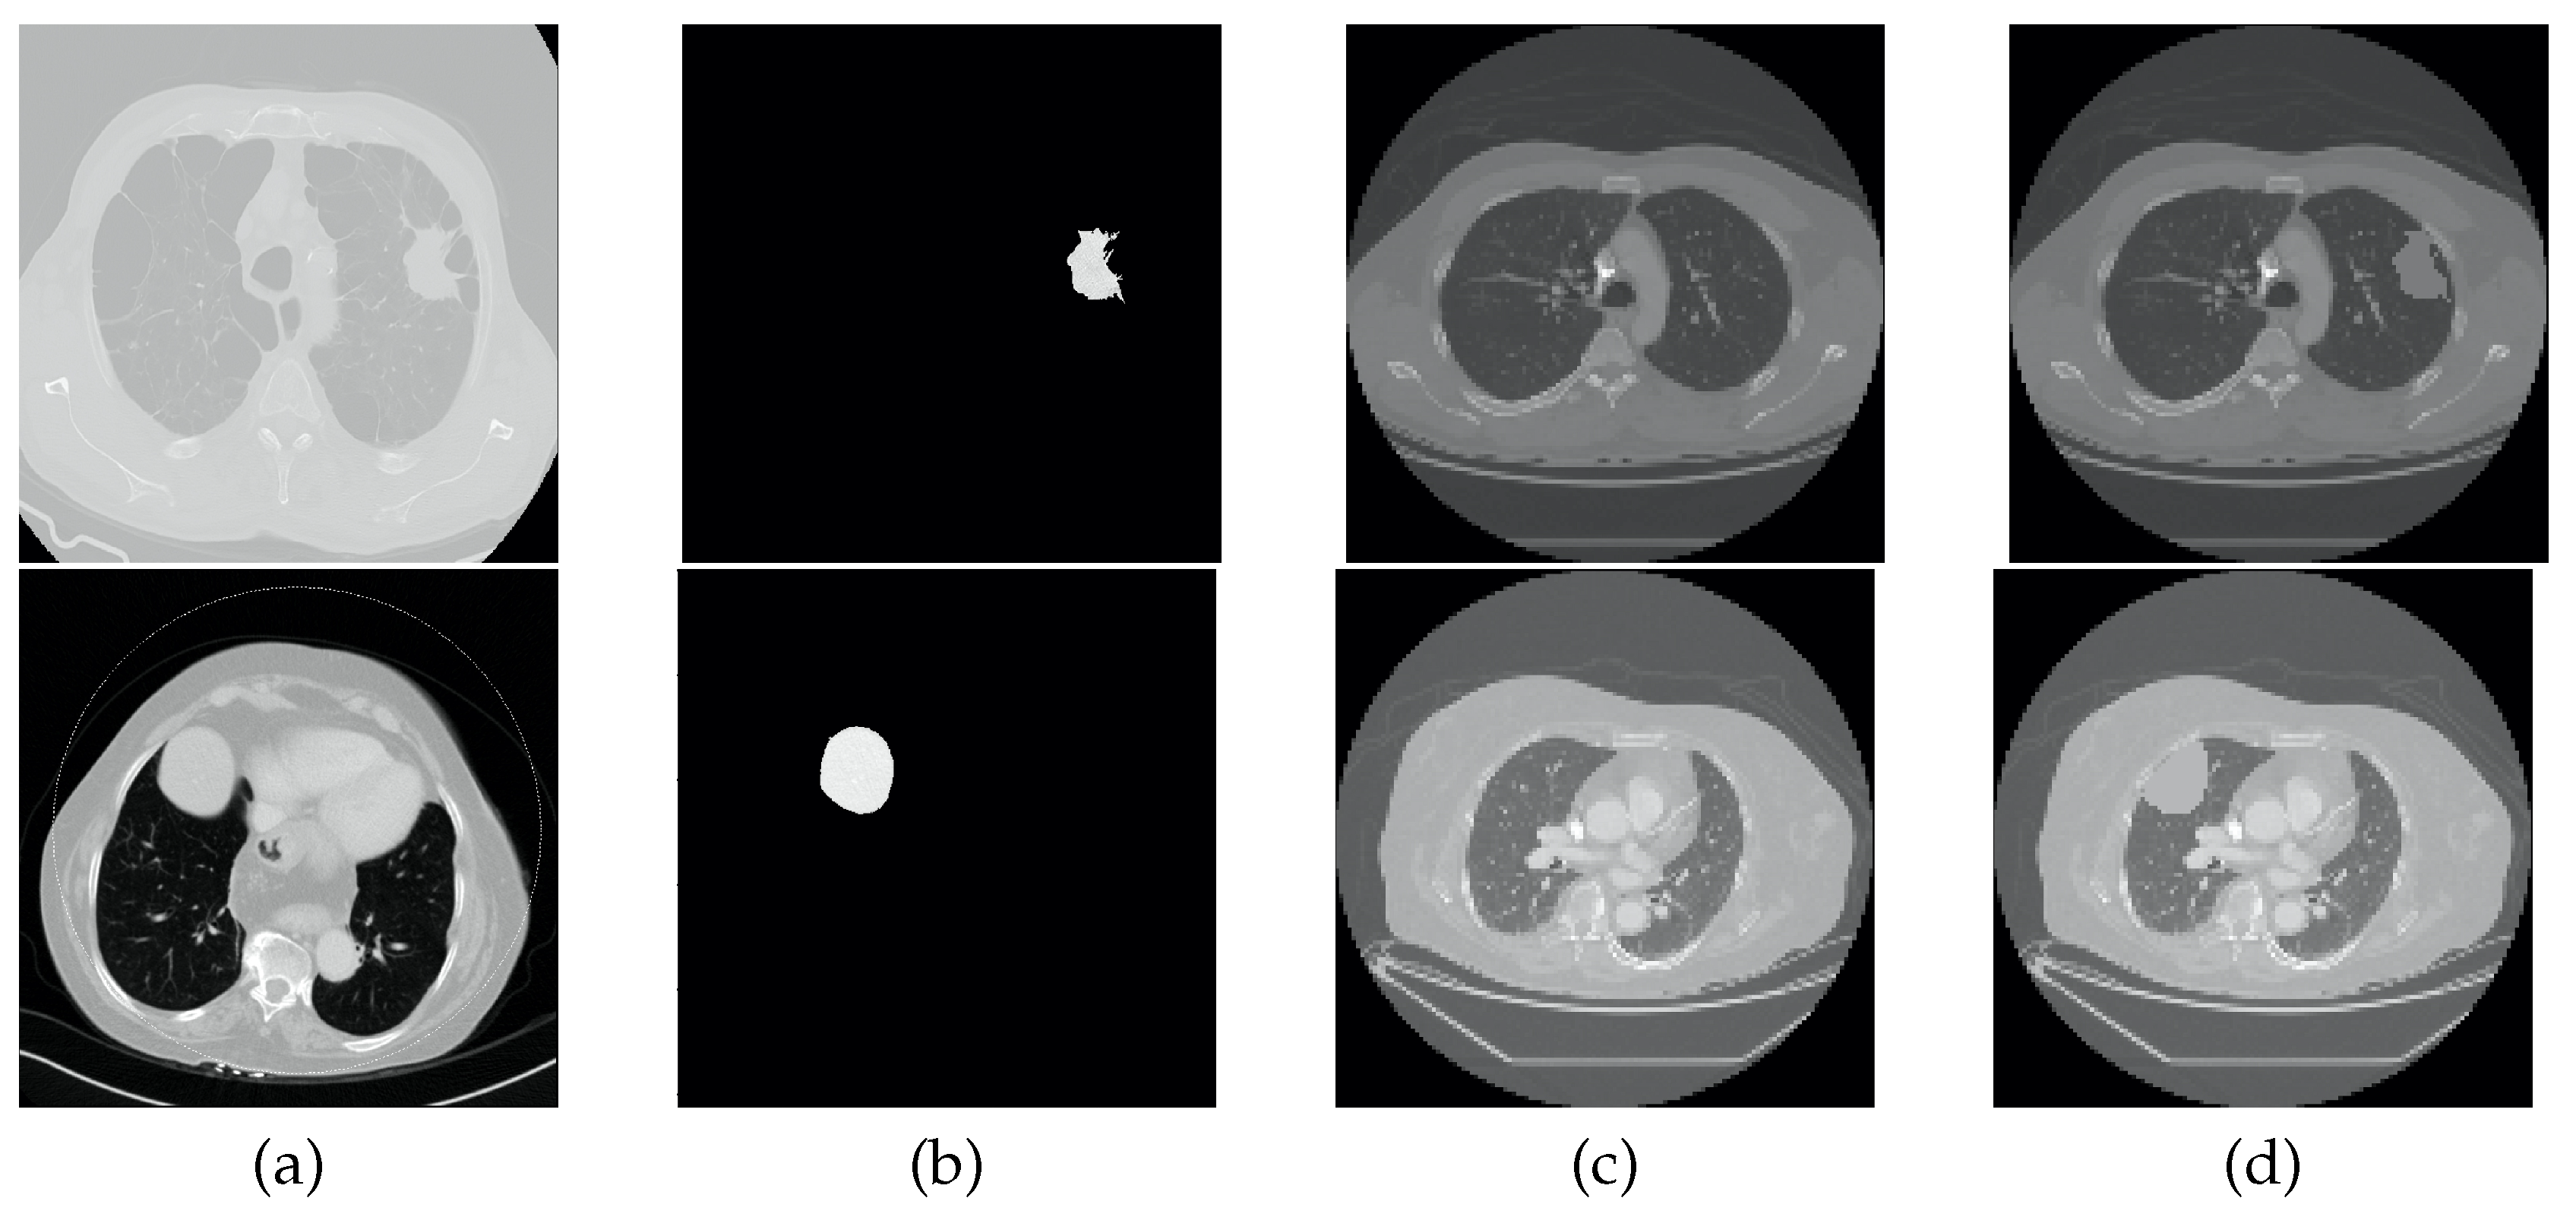

2.2. Mask Segmentation

2.2.1. Original Masks

2.2.2. Mask Correction Protocol

- Including the lung nodules, which, in the majority of cases, appear as a well defined higher density area. Peripheral lung nodules constitute a harder group of nodules to define and, in this case, the key factors were to evaluate the different densities between the chest wall and the nodule, as well to find the fine well-defined line that characterizes the pleura.